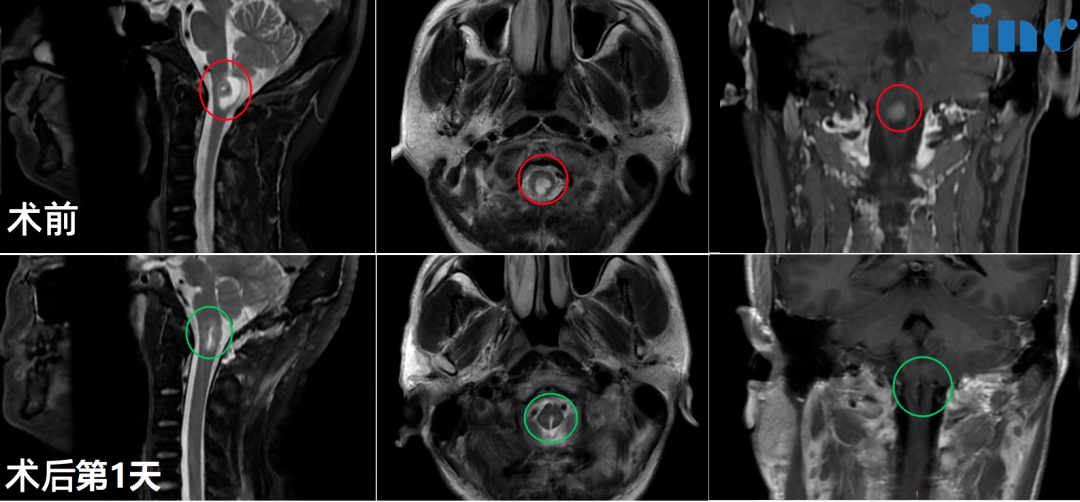

▼30岁女性-脑干海绵状血管瘤

▼20岁女性-胸髓髓内海绵状血管瘤

▼30岁女性-丘脑海绵状血管瘤